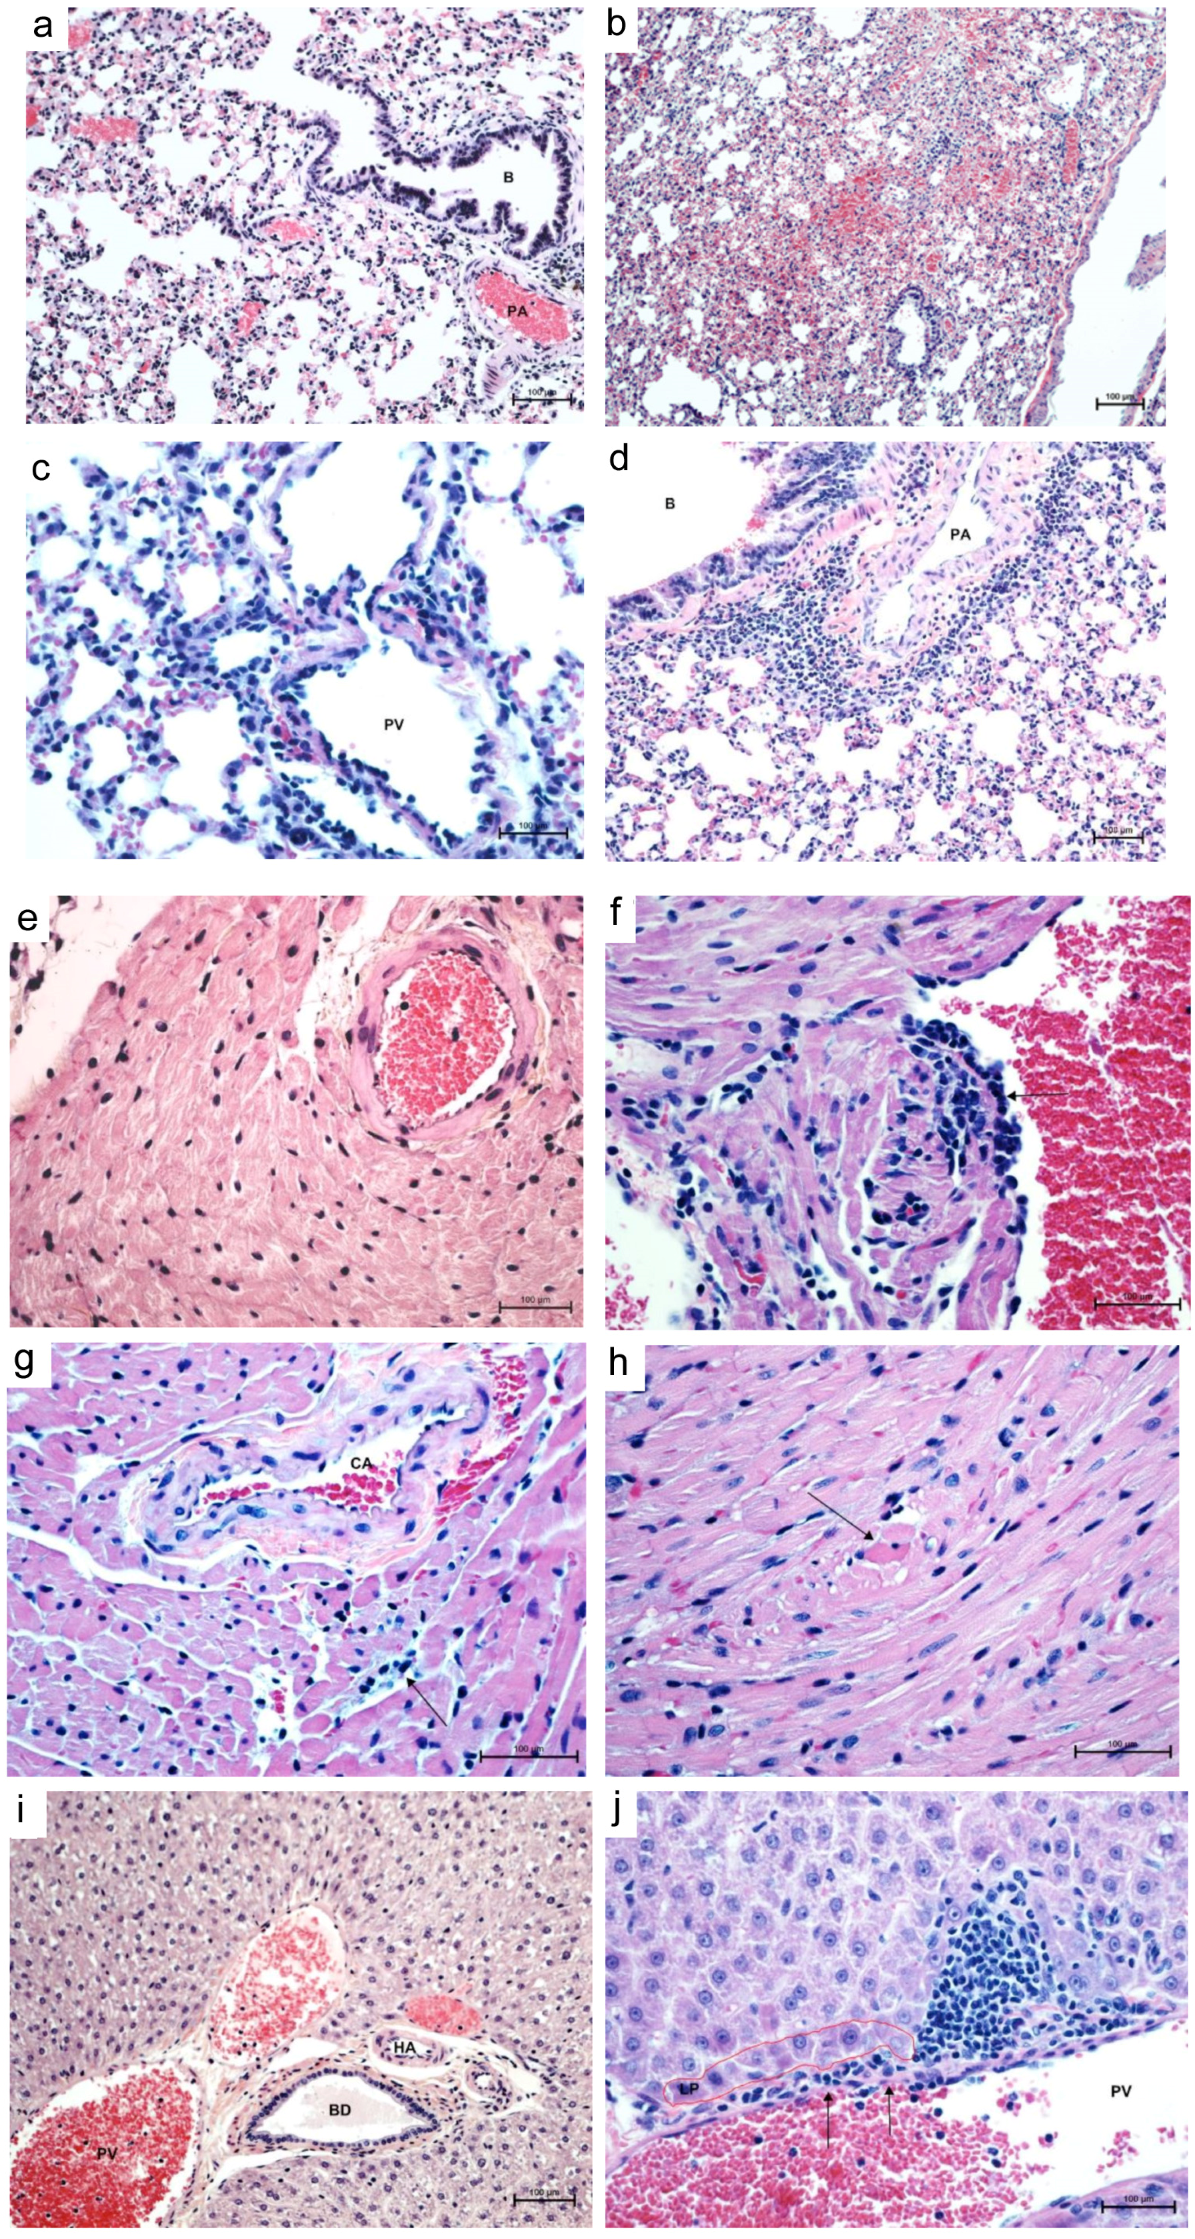

3.2. Histopathology and Immunohistochemistry

| Mouse # | DPI | Lungs | Heart | ||||

|---|---|---|---|---|---|---|---|

| Cong./Ede | MIAH | IP | PBLH | CD/apop | LIM | ||

| DM 1 | 2 | + | + | - | - | - | + |

| DM 2 | 2 | ++ | + | +/− | - | +/− | +/− |

| DM 3 | 4 | ++ | + | +/− | + | +/− | +/− |

| DM 4 | 4 | + | - | - | - | +/− | +/− |

| DM 5 | 7 | ++ | - | + | + | +/− | + |

| DM 6 | 7 | ++ | +/− | + | ++ | + | ++ |

| DM 7 | 14 | +/− | +/− | - | +/− | - | +/− |

| DM 8 | 14 | +/− | ++ | +/− | - | - | +/− |

| DM 9 | 56 | + | +/− | +/− | +/− | - | +/− |

| DM 10 | 56 | + | + | - | - | - | - |